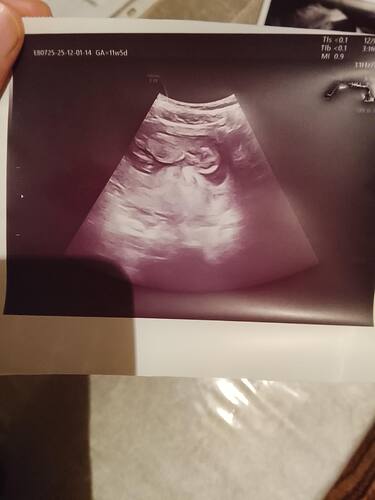

At cnm kaç haftalık oldu

Attımm bakar mısınızzz

Kız bence ya

Erkek gibi duruyo canim Allah bilir yine de boylu boyuna da yatiyo maaşallah Rabbim sağlıklı sıhhatli kucagina almak nasip etsin insallah canım

Kız gibi dedi Nuba göre

Erkek bebiş kuzum

Erkek gibi geldi bana da hayırlısını versin rabbim insallah canim allah sag salim sağlıklı bir sekilde kucagina almak nasip etsin insallah